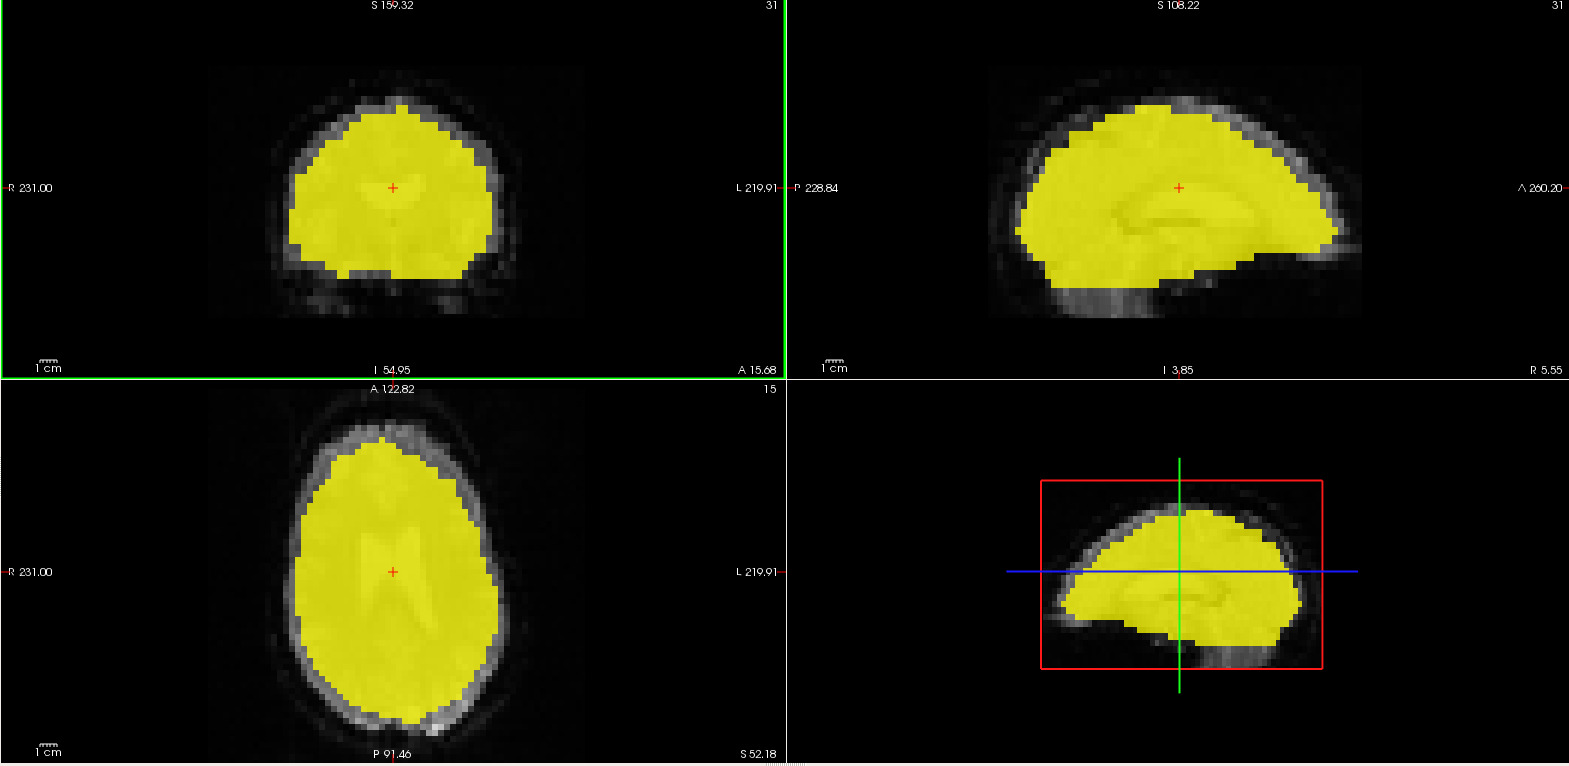

Resampling to Common Spaces and Spatial Smoothing

功能数据保留在native functional space。现在将其采样到公共空间。公共空间是一个geometry,即所有被试要进行体素与体素之间的配准。在FS-FAST有这样的三个空间:

- fsaverage的左半球(fmcpr.up.sm5.fsaverage.lh.nii.gz)

- fsaverage的右半球(fmcpr.up.sm5.fsaverage.rh.nii.gz)

- fsaverage的volume(MNI305 space) - 用于皮层下分析(fmcpr.sm5.mni305.2mm.nii.gz)

每一个都是将整个4D功能数据集重采样到公共空间中。进行重采样之后要进行空间平滑处理,基于2D表面的平滑处理用于表面,3D的用于Volume。查看MNI305空间volume的维度:

mri_info --dim fmcpr.up.sm5.mni305.2mm.nii.gz # 查看数据的维度和slice数量

mri_info --res fmcpr.up.sm5.mni305.2mm.nii.gz # 查看数据的分辨率

76 列76行 93slice的数量 142时间点的数量

2.000 2.000 2.000表示voxel的三个坐标轴上的大小 2000.000=TR。

这个空间的转换是基于 FreeSurfer重建过程中创建的12 DOF talairach.xfm。产看左侧大脑半球的Volume

mri_info --dim fmcpr.up.sm5.fsaverage.lh.nii.gz

mri_info --res fmcpr.up.sm5.fsaverage.lh.nii.gz

1.00 1.00 1.00 2000.000

前三个没有什么意义,因为在surface中没有行,列以及slice。最后一个2000.000表示2s。这个空间的转换时基于FreeSurfer重建过程中产生的基于表面的被试之间的配准。